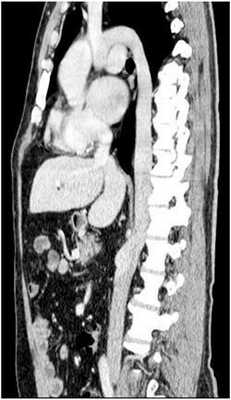

При полисплении, или левом изомеризме [12] возможны следующие аномалии развития: оба легких состоят из двух долей, оба предсердия имеют морфологию левого, выявляются множественные селезенки, аплазия нижней полой вены с дренированием в непарную вену (рис.3), врожденные пороки сердца, удвоение верхней полой вены или её отсутствие.

Рис.3. СКА сосудов брюшной и грудной полостей (справа – фронтальный, слева - сагиттальный срез). Аплазия предпочечного и печеночного отделов нижней полой вены с дренированием в непарную вену, полиспления.